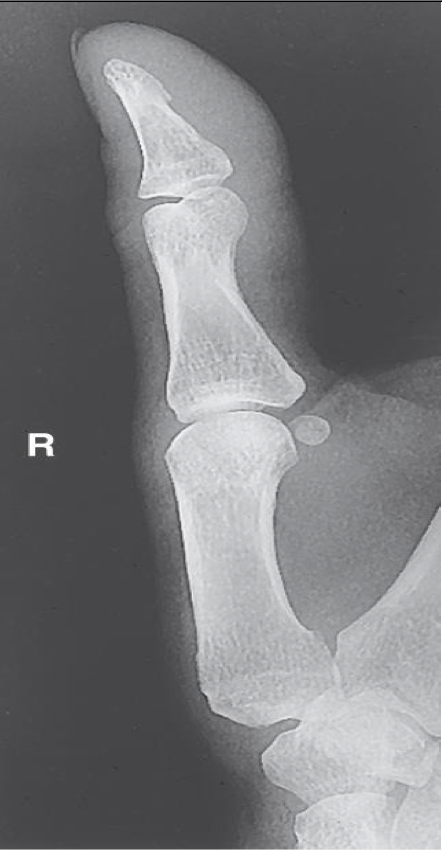

AP Thumb ( 1st Digit)

Evaluation Criteria for AP (PA) Thumb ( 1st Digit)

• Entire thumb demonstrated (including first CMC joint)

• No soft tissue overlapping MCP

• Center field at first MCP joint

• Must include trapezium

• No rotation of phalanges

• Equal concavity and soft tissue